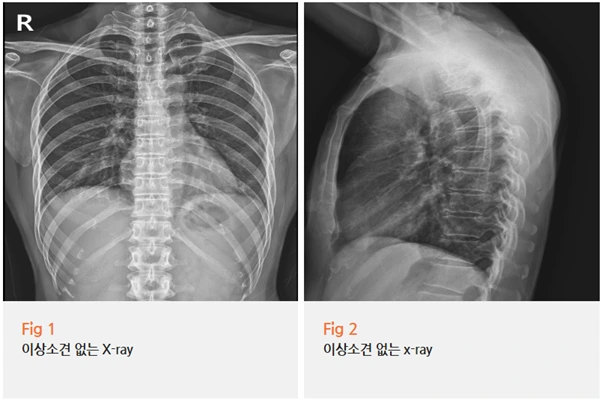

내원하신 당일 엑스레이와 초음파 검사를 시행했어요.

다행히 골절 소견은 없었어요.

그런데 저는 검사 결과를 보면서 단순 근육통이라고 넘어가기 어렵다고 판단했어요.